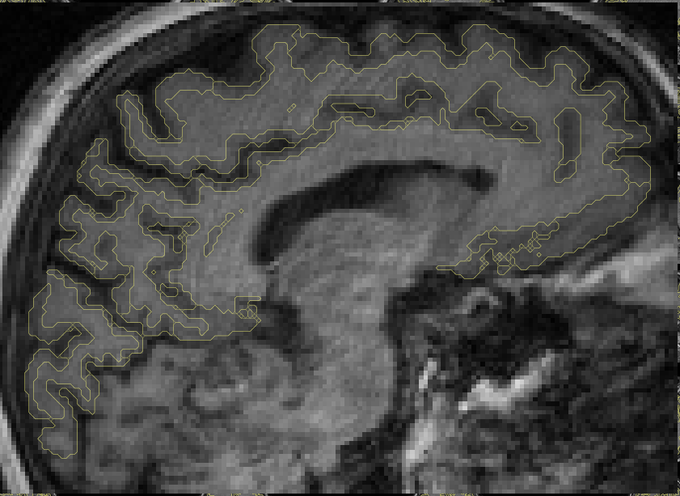

Just learning about SurfIce, looks quite useful: https://t.co/WBsWLGMWlw

More from the Chris Rorden's lab:

https://t.co/tBsw3XLSfe

man, tool discovery is still hard! so many academic "walls" and gaps .. #opensource

@relajoie it appears lack of contrast/boundary leading to the cerebellum